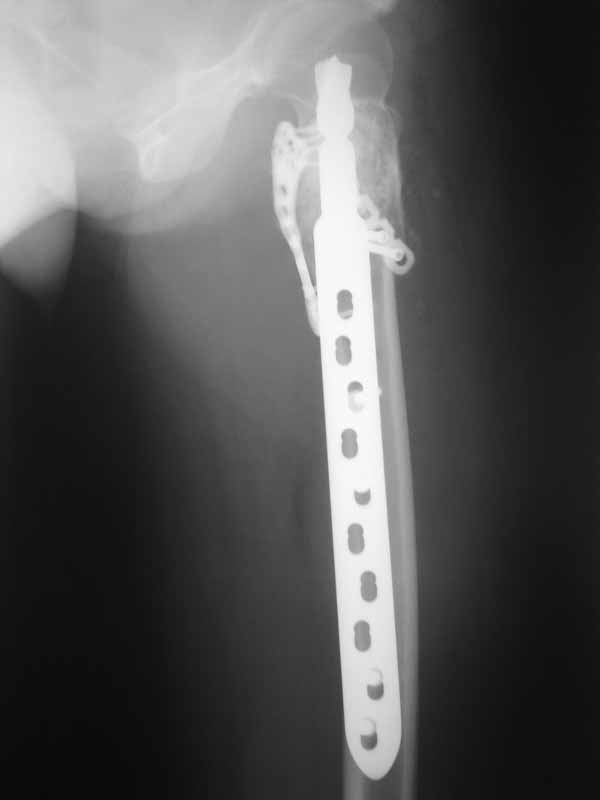

А по пациентке:Обследования провели в легких чисто, лабораторно - без особенностей. Выполнили МРТ - костная киста, однокамерная. Оперирована - створчатая остеотомия, удаление кисты, костная пластика аутокостью с гребня подвздошной кости, остеосинтез DHS со сприральным клинком, створка фиксирована пластинами монокортикально. Макроскопически - слизеподобное содержимое темно-бурого цвета, отдали на гистологию.